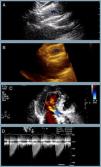

At one-year follow-up the patient remains in NHYA class II, with NT-proBNP level of 510 pg/ml. Transthoracic echocardiography revealed the two bioprostheses overlapping with appropriate transprosthetic gradients and associated mild to moderate leak (Figure 2).

The last transthoracic echocardiography (at one-year follow-up) revealing (A and B) partial overlapping of the two bioprostheses (blue asterisk) (two- and three-dimensional respectively); (C) mild to moderate associated periprosthetic leak; (D) appropriate transprosthetic gradients (maximum and mean of 20 mmHg and 10 mmHg, respectively).